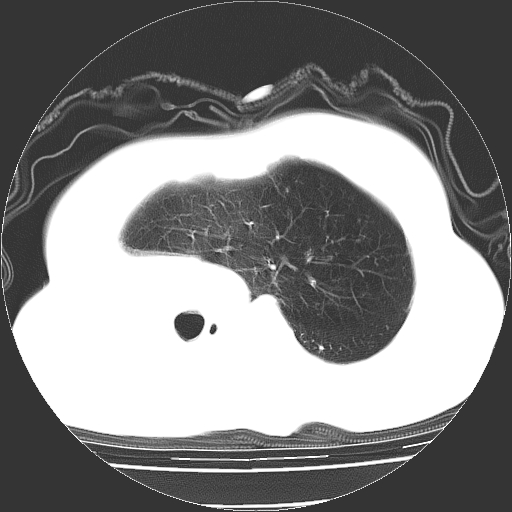

标题: CT23991:女,72岁,咳嗽、憋气一周。 [打印本页]

女,72岁,咳嗽、憋气一周,十年前曾患肺结核及胸膜结核。

右侧毁损肺,右侧纵隔疝,左肺代偿!

右侧肺硬变,左肺代偿气肿。

1.右侧损毁肺伴胸膜钙化,2.左肺小结节灶,良性可能大,注意复查。3.肝脏左叶囊肿。4.先天性一侧肺不发育待出外(右侧胸廓无明显塌陷)。对比原片应该非常有帮助。

右侧肺毁损,左肺代偿性肺气肿,纵隔疝。